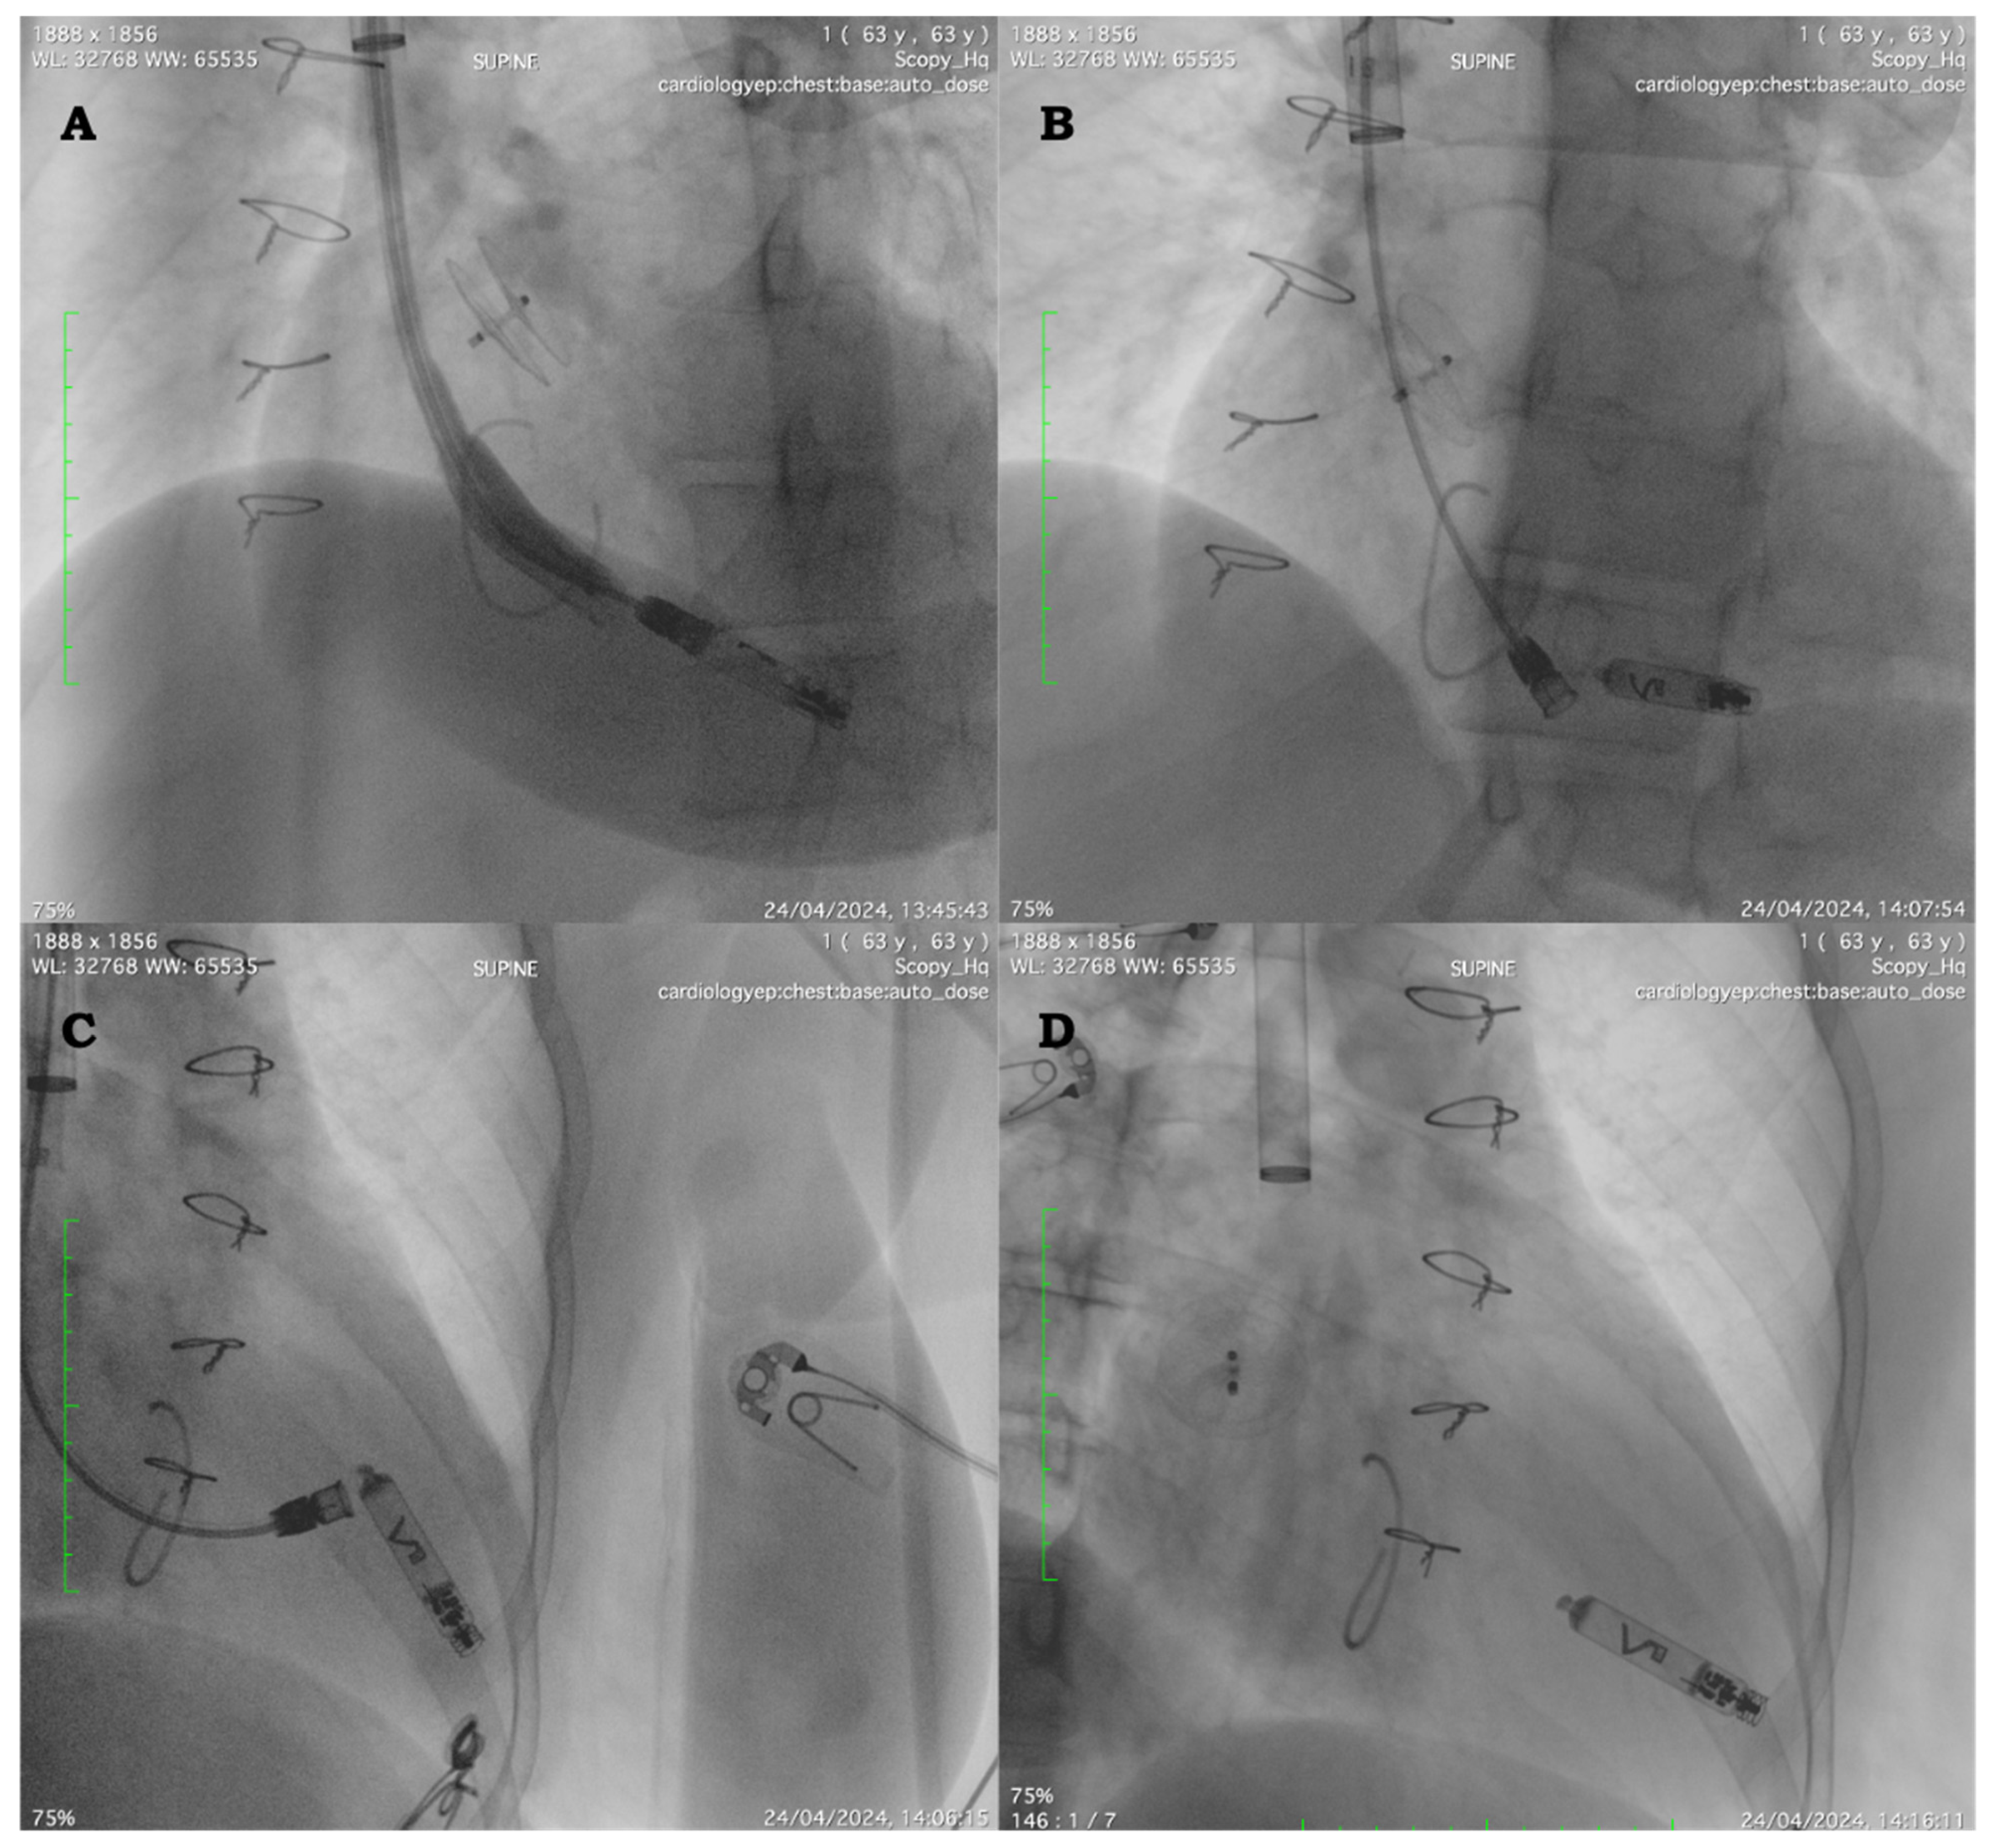

The procedure was performed in the fasting state and under moderate conscious sedation with intravenous boli of midazolam hydrochloride (0.03–0.05 mg/kg) and fentanyl citrate boli (0.7–1.4 mcg/kg) for short-term analgesia plus continuous infusion of dexmedetomidine. After the patient was prepped in a sterile fashion, mepivacaine 1% was used to infiltrate the skin between the two heads of the sternocleidomastoid muscle. Ultrasound-guided right jugular venous access was obtained utilizing the Seldinger technique, and a super-stiff Amplatz wire (Boston Scientific, Malborough, MA, USA) (180 cm, 0.035 cm) was passed through the 8 Fr sheath and advanced down to the inferior vena cava. Consecutive up-sizing via a 4 Fr size increase to a 24 Fr dilator was performed. Finally, the 27 Fr (outer diameter) Abbott Aveir sheath was passed over the wire into the mid-right atrium. Subsequently, the Aveir, on a deployment catheter (23 Fr), was passed through the 27 Fr outer sheath and moved across the TV at first into an apical RV septal position under fluoroscopic and echocardiographic guidance. Despite the good fluoroscopic position on angiograms and satisfactory R-wave sensing (7.6 mV), pacing impedance and thresholds were suboptimal on contact mapping before active fixation (3.5 V @ 0.4 ms). A second attempt was made at a higher position, and the device was deployed after a good contact mapping test with the current proprietary program surface analyzer using conductive telemetry with skin electrodes connected to the patient’s torso. The final threshold was stable at 1.25 V @ 0.4 ms, with stable impedance and good RV sensing (6.4 mV). The stability test and final position are shown in Figure 1A–D. At the end, a figure-of-eight suture was placed to remove the introducer.

Figure 1.

(A) Left anterior oblique (LAO) 30 degree. Position of the leadless device on the septum. The tricuspid valve annulus and the atrial septal closure device are evident. (B) LAO 30 degree. Stability testing after leadless device implantation. (C) Right anterior oblique (RAO) 30 degree. Stability testing after leadless device implantation. (D) RAO 30 degree. Final position after delivery system release.